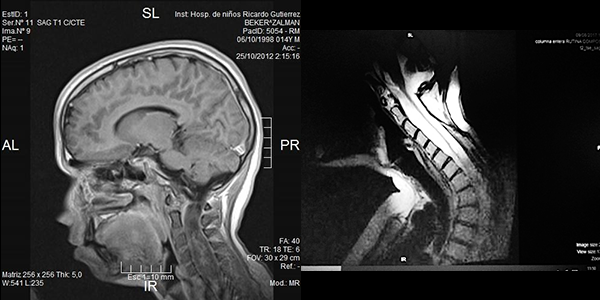

Se registraron dos reoperaciones ( casos 3 y 5 ). En el Caso 5 el paciente experimentó un empiema en el lecho quirúrgico y requirió retiro de la laminoplastía, lavado del foco infeccioso y tratamiento antibiótico por tres semanas, este paciente con Grado 3 en la escala de McCormick se mantuvo con Grado V de la misma escala de manera irreversible luego de un año de la cirugía. El caso 3 se trató de un tumor del cono medular diagnosticado inicialmente como Ependimoma Mixopapilar de la Cola de Caballo (Grado I OMS) en el que observó un residuo sobre la cara anterior medular en una IRM de control (Figuras 1 y 2). La reexploración evidenció la ubicación intramedular de la lesión y la revisión anatomopatológica definitiva concluyó que se trataba de un Ependimoma (Grado II OMS).

Figura 1: Caso 3. Ependimoma Dorsolumbar. Residuo cara anterior

Figura 3: Caso 10. Ependimoma cervical pre operatoria: Lesión sólida C3 y dilatación siringomiélica. Posoperatorio: resección completa, disminución de la cavidad. Restos hemáticos decantados.